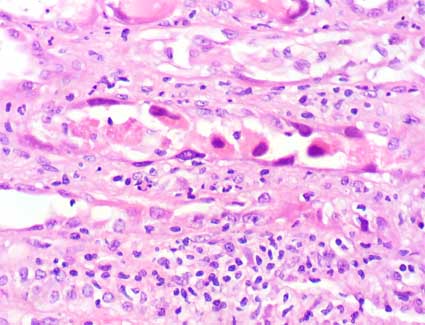

Figura 2.

H&E, X200.